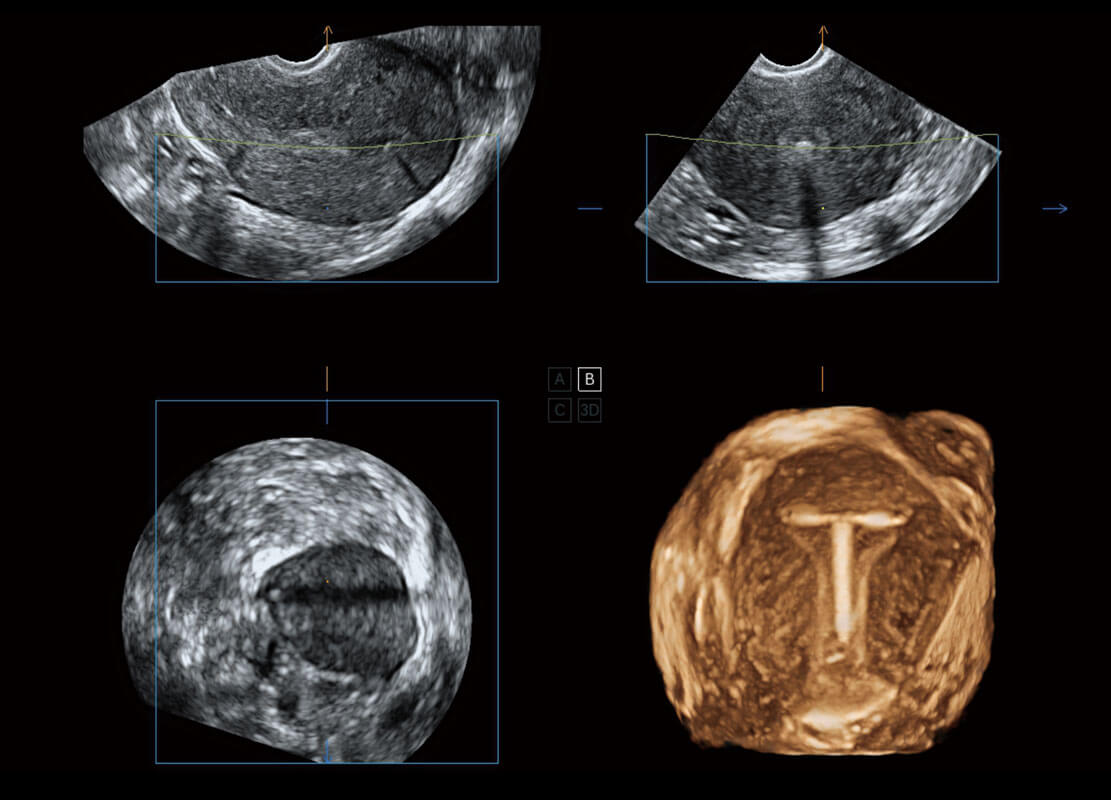

生殖健康

P60卓越的图像质量搭载专科探头,在妇科基础疾病的诊断、卵泡生长的监测、输卵管通畅情况的判别等方面为您提供全面的生殖应用方案。

• 腔内妇科-宫腔分离

• 腔内妇科-卵巢

• 腔内三维-宫内节育器

• 腔内三维-光影成像